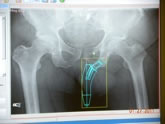

| Pre-op templating |

His own templating process |

Determining neck resection |

Photos from His First Case

JISRF is pleased that Dr. Mackel has agreed to help define the indications and contraindications on Neck Stabilized Stems for THA and as part of that process, what are the learning curves to preoperative planning (templating). Lateral templating appears to be key in determining stem size and A/P helps to determine level of neck resection (leg length) and femoral offset. |